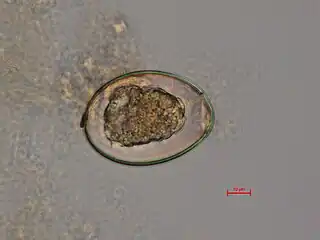

a-c)Diphyllobothrium sp. eggs -

Diphyllobothrium latum - fertilized egg

Microscopy

Diagnosis is usually made by identifying proglottid segments, or characteristic eggs in the faeces.[15] Eggs are usually numerous and can be demonstrated without concentration techniques. Morphologic comparison with other intestinal parasites may be employed as a further diagnostic approach.These simple diagnostic techniques are able to identify the nature of the infection to the genus level, which is usually sufficient in a clinical setting. Though it is difficult to identify the eggs or proglottids to the species level, the distinction is of little clinical importance because - like most adult tapeworms in the intestine - all members of the genus respond to the same treatments.[8][16][17]